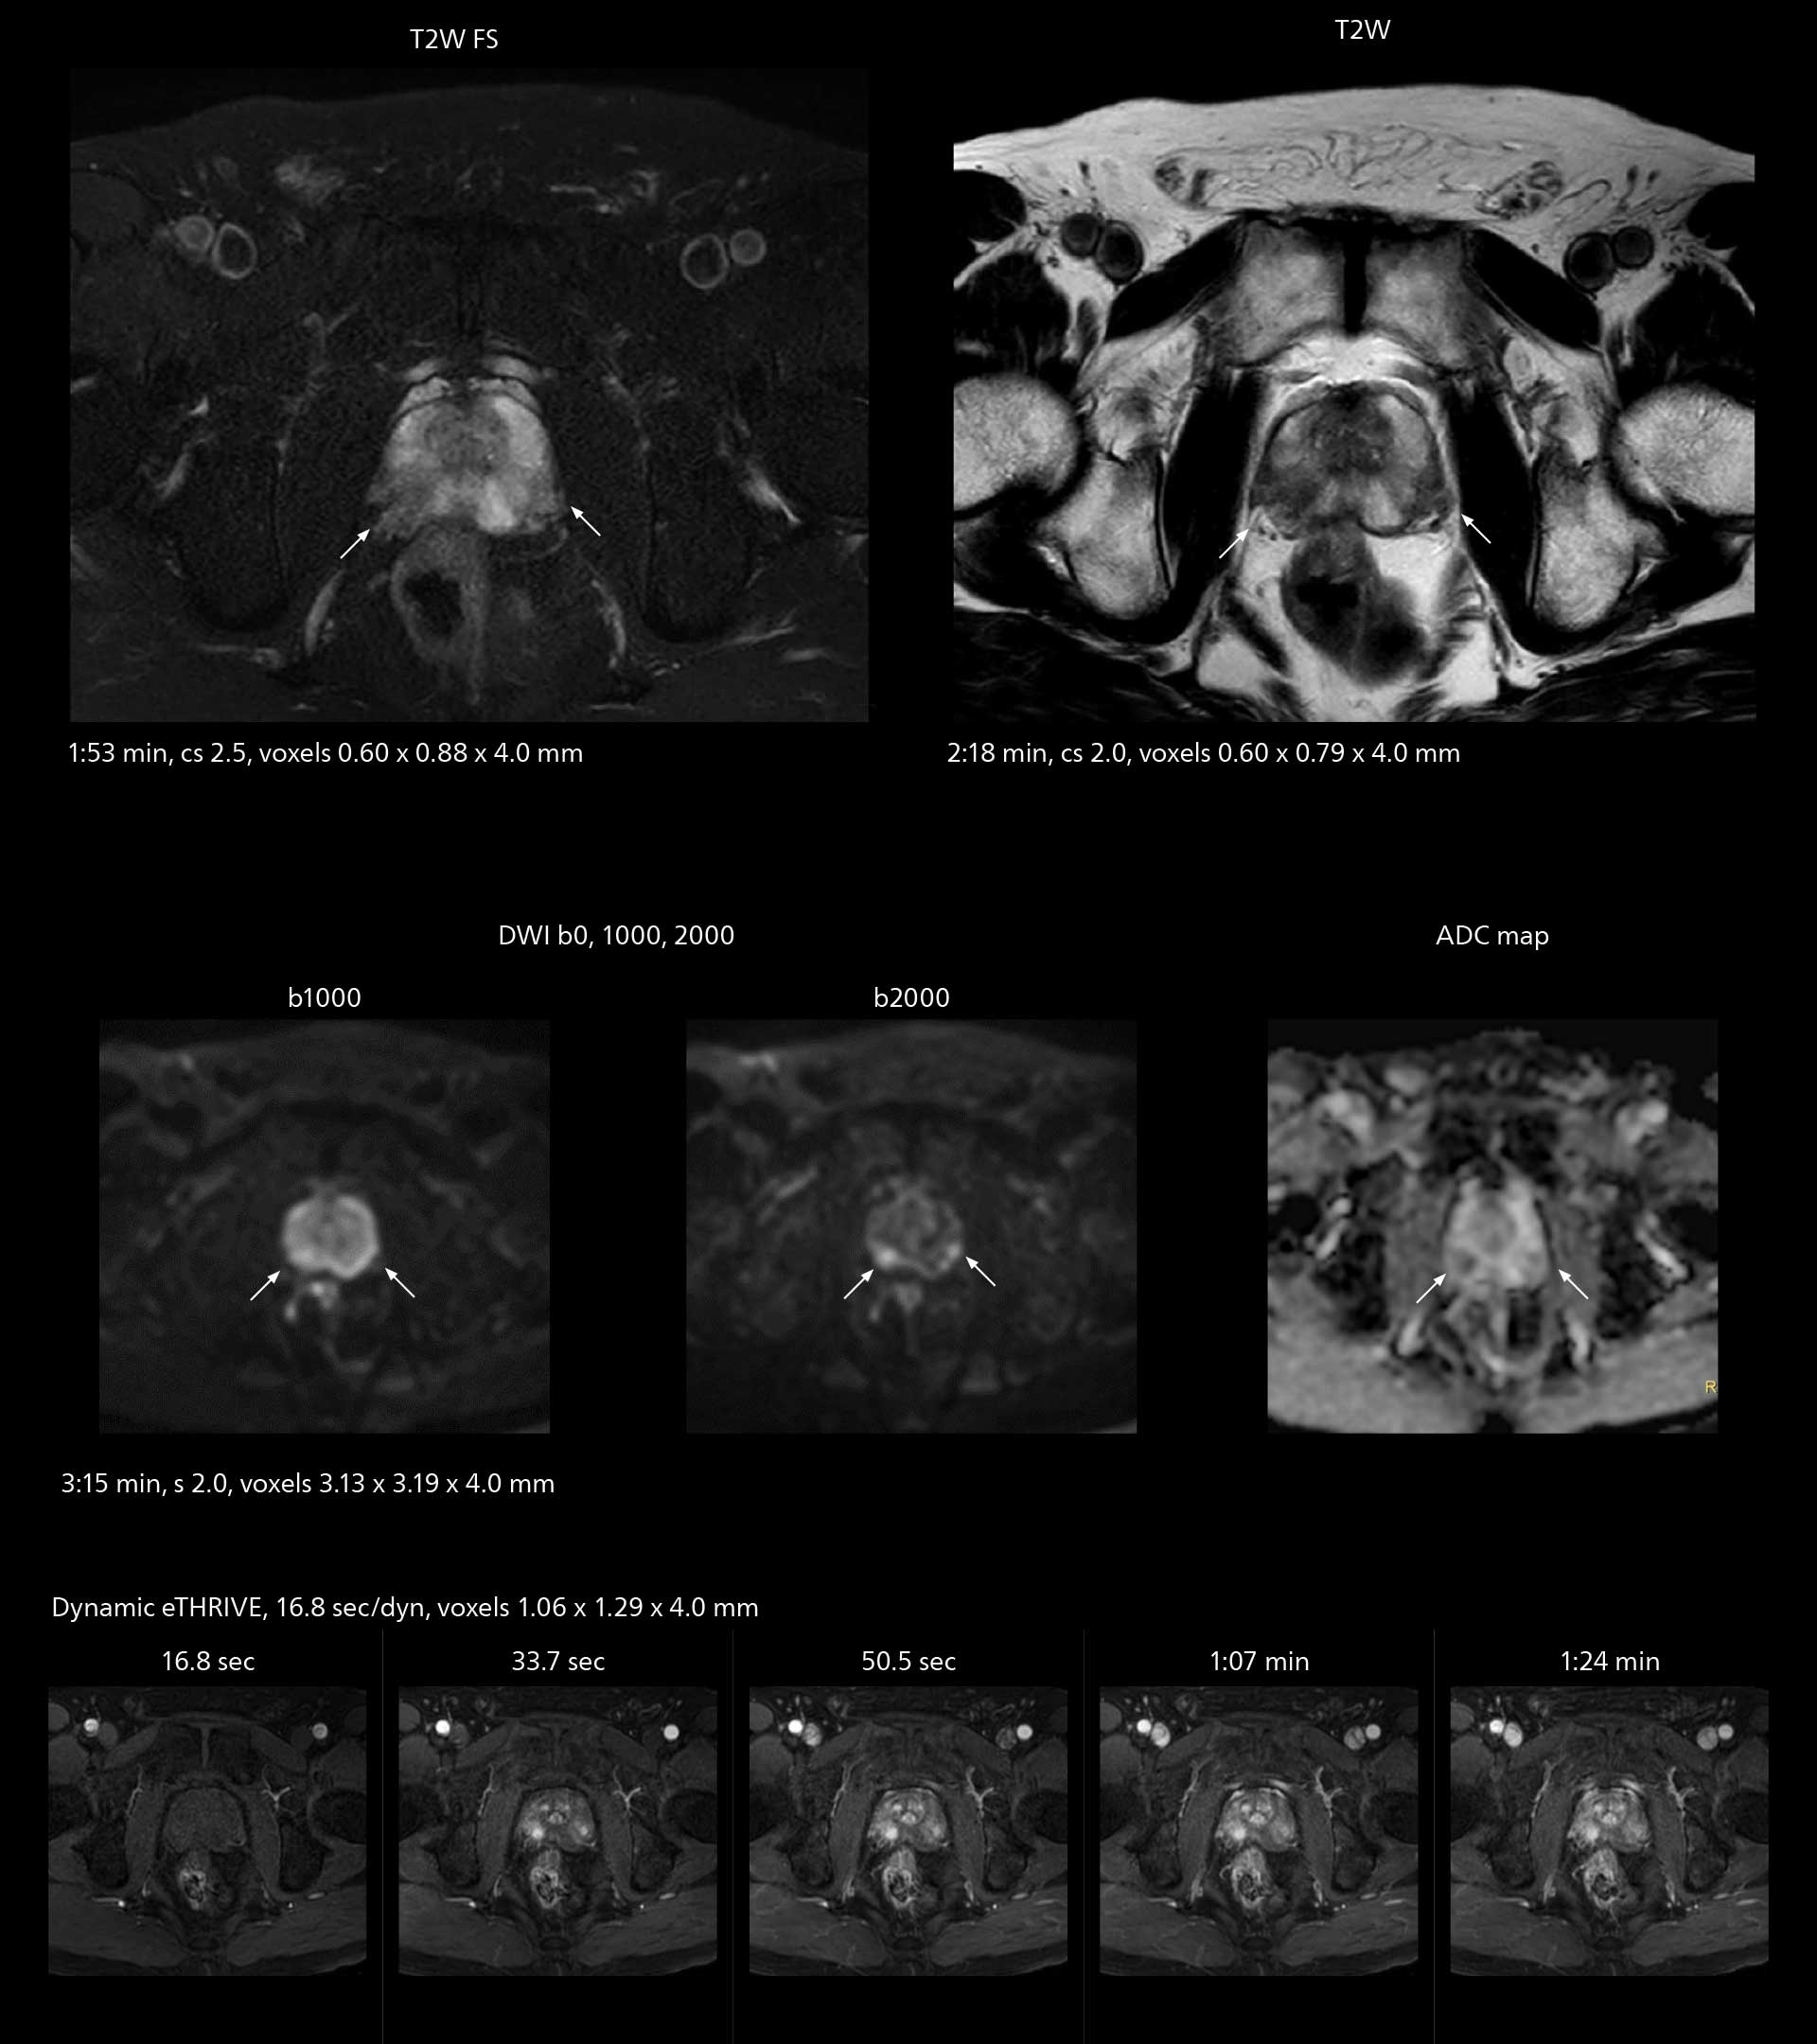

Examples of prostate imaging showing faster scan times and improved resolution illustrate the power of SmartPath to Elition X in this case of prostate cancer with PI-RADS score 4.